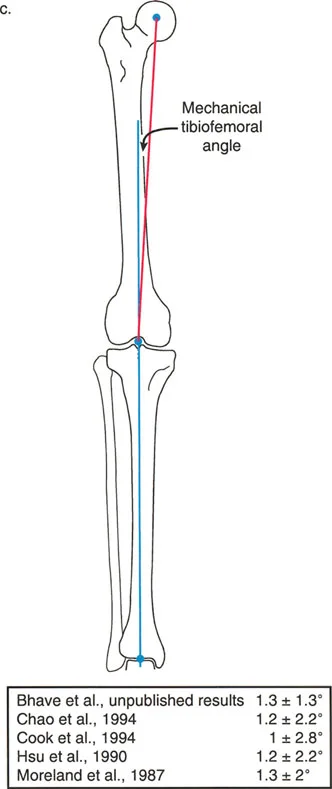

The Mechanical Axis

The mechanical axis of a bone is a straight line connecting the center points of its proximal and distal joints. It represents the true mechanical lever arm of the bone during weight-bearing activities.

- Femur: The mechanical axis line is drawn from the center of the femoral head to the center of the knee joint. The center of the knee joint is specifically defined as the center of the femoral notch or the midpoint between the tibial spines.

- Tibia: The mechanical axis line is drawn from the center of the tibial plateau to the center of the tibial plafond (the ankle joint).

- Lower Limb Overall: The mechanical axis of the entire lower extremity is a line connecting the center of the femoral head to the center of the ankle joint. In a normally aligned limb, this line passes just medial to the center of the knee joint.

Mechanical Axis Deviation MAD

Mechanical Axis Deviation (MAD) is the perpendicular distance from the mechanical axis of the entire lower limb to the center of the knee joint. It is the definitive test for global limb malalignment.

- Normal MAD: The mechanical axis normally passes slightly medial to the exact center of the knee joint. The normal MAD is approximately 8 mm (± 7 mm) medial to the center of the knee.

- Pathologic MAD: A mechanical axis passing excessively medial to the knee center indicates a varus alignment. This predisposes the patient to medial compartment osteoarthritis due to pathologic compressive forces. Conversely, a mechanical axis passing lateral to the knee center indicates a valgus alignment, predisposing the patient to lateral compartment osteoarthritis.